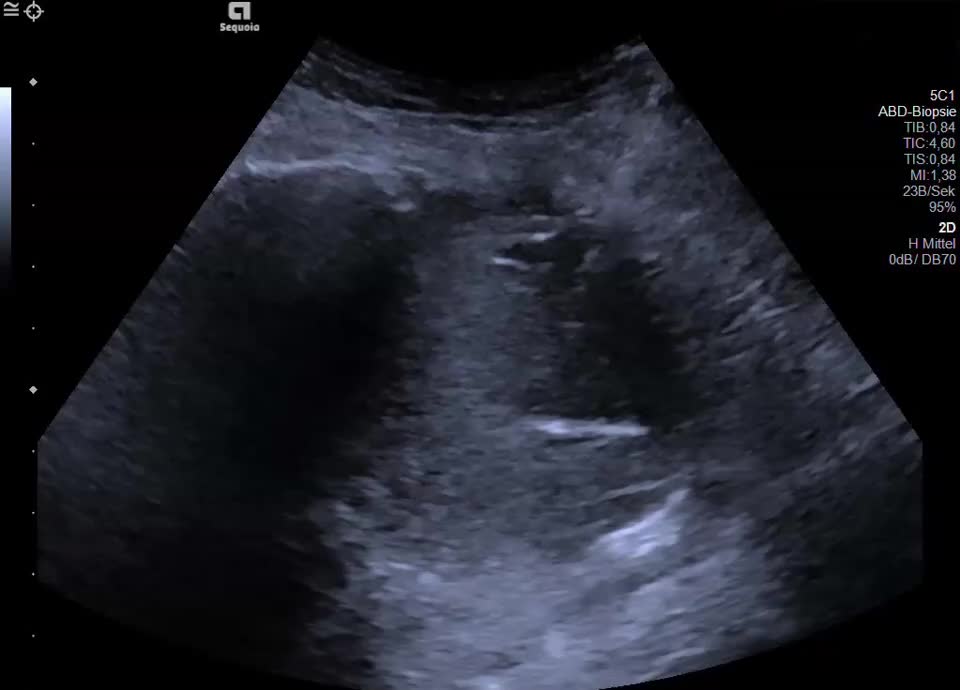

Retroperitoneum

• Psoas metastasis of urothelial carcinoma

• Biopsy of psoas metastasis (video)